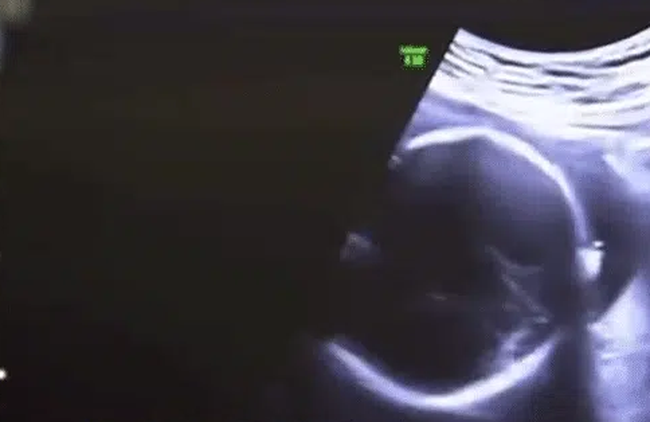

Bác sĩ cho hay, họ đã tiến hành siêu âm cho cô Lý và không phát hiện sự tồn tại của tử cung, ngoài ra kết hợp với tiền sử không có kinh nguyệt trong nhiều năm của cô Lý, họ đã tiến hành kiểm tra nhiễm sắc thể đối với cô ấy.

Trong quá trình kiểm tra nhiễm sắc thể, cô Lý được kết luận là nhiễm sắc thể 46XY. Để ngăn cản viêm tinh hoàn trở thành ác tính, cô Lý đã tiến hành phẫu thuật, tình trạng cũng đang dần hồi phục, không ảnh hưởng đến sức khỏe và tính mạng.